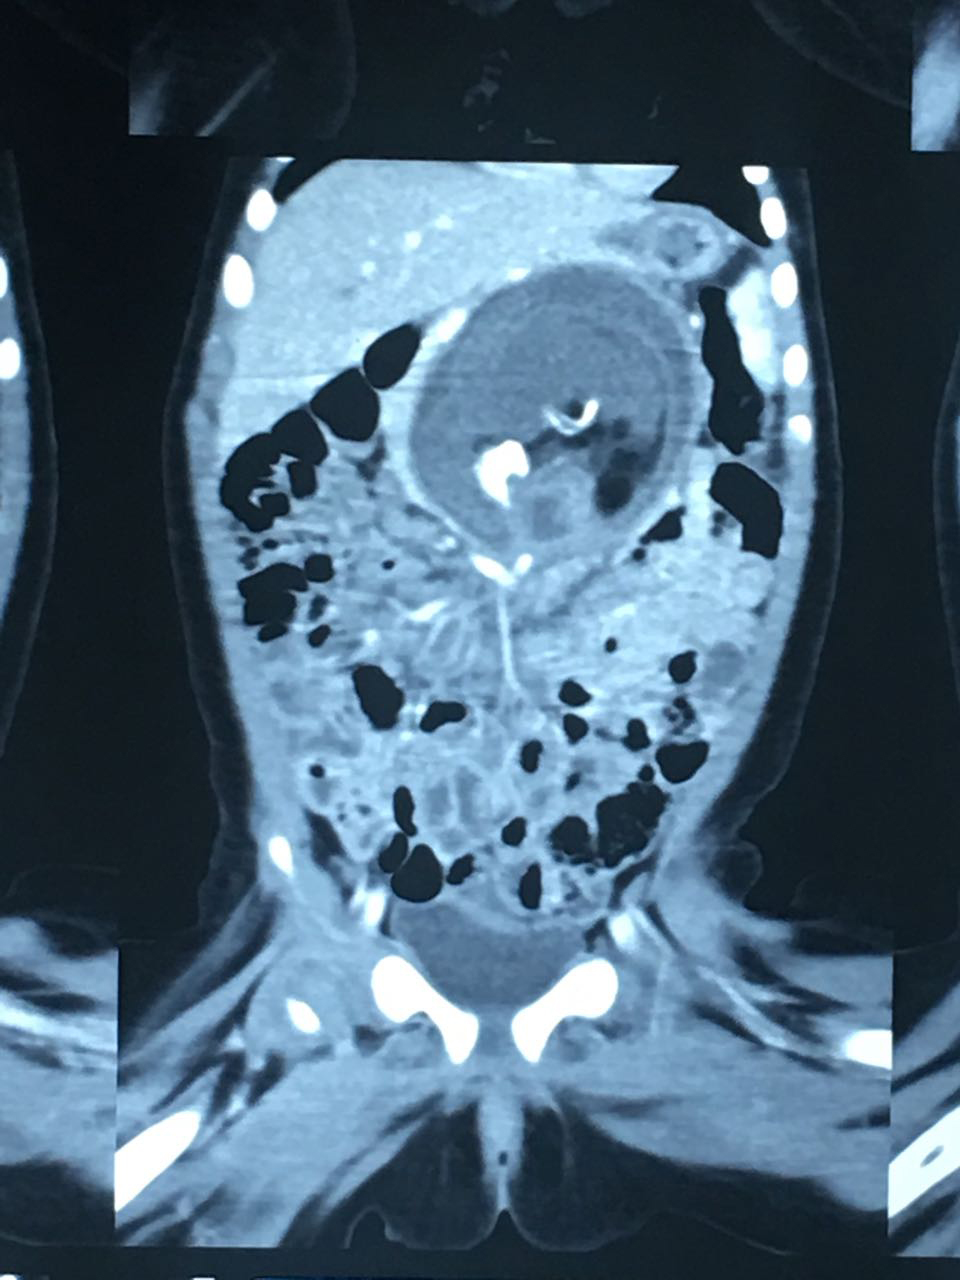

Foetus-In-Fetu (3)